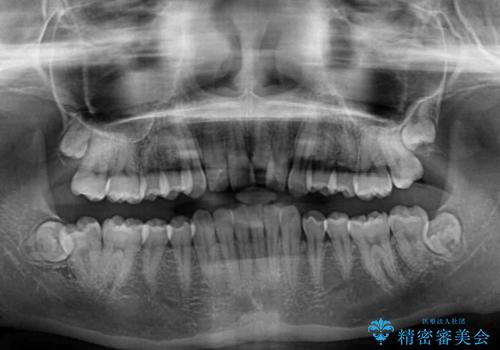

- 前歯のデコボコ気になるとのことで来院された患者様です。

下顎骨が上顎骨に対して右側にシフトしており、さらに下顎が後方に位置しているため、非常に強い咬合力で食いしばっている状態でした。

上下顎ともに歯列全体の後方移動とIPR(歯と歯の間を削る)によってデコボコが解消するように設計し、インビザラインにより治療を行うこととしました。

強い咬合力による臼歯部の噛みにくさと、それに伴う歯の移動の鈍さに悩まされ、非常に長い期間を要することとなりました。

上下正中位置は、治療開始時よりは改善したものの、ここが限界であろうというところでのゴールとなりました。